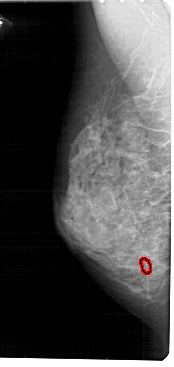

A_1897_1.LEFT_MLO

LEFT_MLO LINES 5491 PIXELS_PER_LINE 2596 BITS_PER_PIXEL 12 RESOLUTION 43.5 OVERLAY

FILE: A_1897_1.LEFT_MLO.OVERLAY

TOTAL_ABNORMALITIES 1

ABNORMALITY 1

LESION_TYPE CALCIFICATION TYPE PLEOMORPHIC DISTRIBUTION CLUSTERED

ASSESSMENT 4

SUBTLETY 3

PATHOLOGY MALIGNANT

TOTAL_OUTLINES 1

BOUNDARY